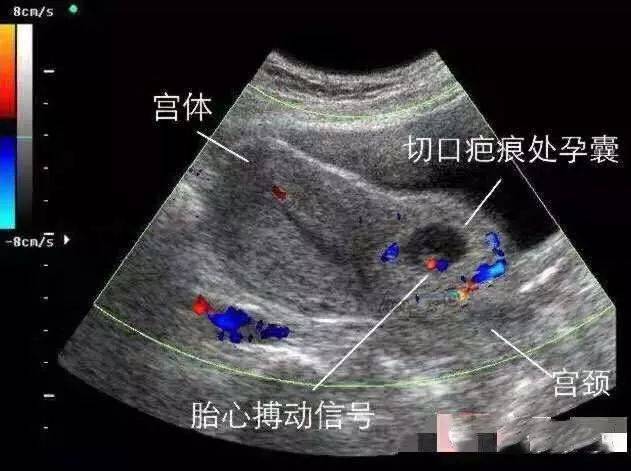

瘢痕妊娠图片,瘢痕子宫图片

瘢痕妊娠超声图片

疤痕妊娠b超图片

子宫瘢痕妊娠超声图片